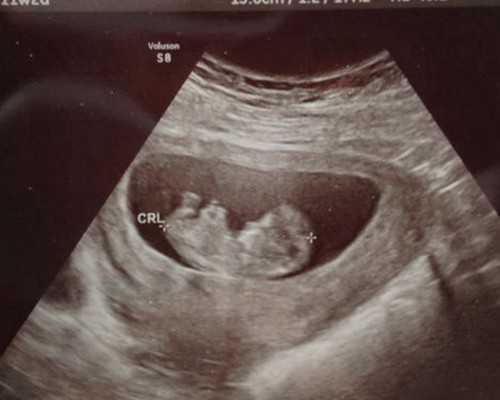

江西供卵二代试管婴儿包成功费用多少钱?二代试管婴儿生男孩费用10万够吗?在团队中,有一部分女性需要在体外受精(IVF)技术中捐献(借用)卵子来实现生育。可见供卵二代试管婴儿是生育路上最后的法宝。目前供卵二代试管婴儿技术在江西省18家医院开展。对于江西省很多想做供卵二代试管婴儿的患者来说,他们最关心的就是供卵生男孩包成功的费用问题。今天就和小编一起来了解一下吧。